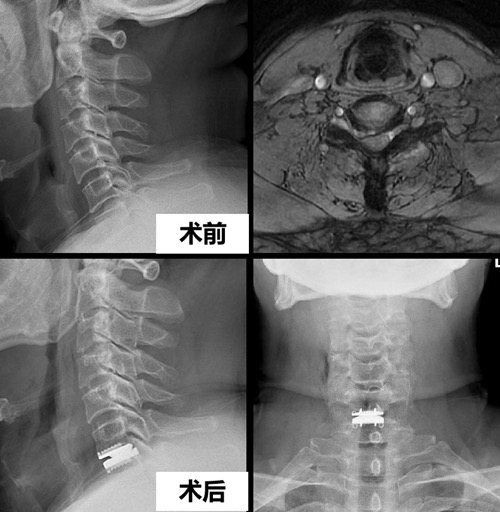

据介绍,该例手术患者60岁,半年前出现肩颈部疼痛,同时伴有右手疼痛和麻木,先后尝试各种保守治疗方法,但症状未见明显缓解。就诊1个月前,患者右上肢疼痛和麻木的症状明显加重,严重影响睡眠。为彻底解决这一问题,该患者慕名至华西医院刘浩教授门诊就诊。刘浩教授仔细阅片后发现其颈6/7椎间盘向右突出明显,像一块大石头一样严重压迫其右侧神经脊髓及神经根。刘浩教授结合病史、体检及影像学资料,确诊其为 “颈6/7椎间盘突出症伴不全脊髓神经损害”,建议患者入院进行手术治疗。从入院时的忐忑不安到出院时的平复如故,该患者住院时间仅为24个小时。

患者住院时间虽然只有短短24个小时,但这背后却是刘浩教授30余年深耕临床一线七千多例脊柱手术与治疗上千例疑难重症的经验积累,是刘浩教授团队不断突破多项技术壁垒、不断坚持技术创新的结果。在认真对待每台手术、积累大量临床经验的基础上,刘浩教授创新解决了椎管内和颈部软组织彻底止血的难题,探索出了国内独有的颈椎前路手术后“无引流管”“无尿管”技术,使患者术后早期下床无管道限制,同时降低患者术后疼痛及感染风险,减少置管后留下的创伤与手术瘢痕,大大优化了患者的术后体验,为颈椎前路手术日间化创造了条件和基础。